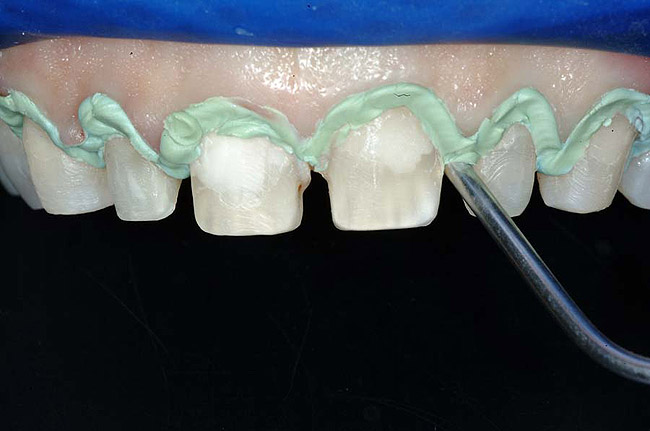

Figure 4 To ensure adequate cervical access and promote hemostasis, a viscous, gingival retraction paste containing aluminum chloride (Expasyl™, Kerr Corporation) was placed in the sulci surrounding the preparations.

For example, before initiating the cementation process, preparations must be thoroughly cleansed (Figure 3), and adequate hemostasis and isolation should be ensured (Figure 4). Although newer generations of adhesives have been shown to be more tolerant of saliva contamination,7 proper isolation and hemostasis are still advisable because saliva and blood contamination cannegatively influence the bond strength of some bonding systems.8,9 Also,consider that resin cements are preferred for esthetic restorations, including porcelain laminate veneers.10,11 Successful use of these cements is dependent upon the incorporation of proper ceramic conditioning and tooth-surface treatment (ie, multiple-step total etch or self-etch adhesive)(Figure 8');" rem="#ip:figure5 through Figure 8">Figure 5 through Figure 8) to avoid incompatibility issues with the chosen cement and/or enhance the mechanical interlocking that occurs between the porcelain/resin-cement/tooth interfaces.10-13